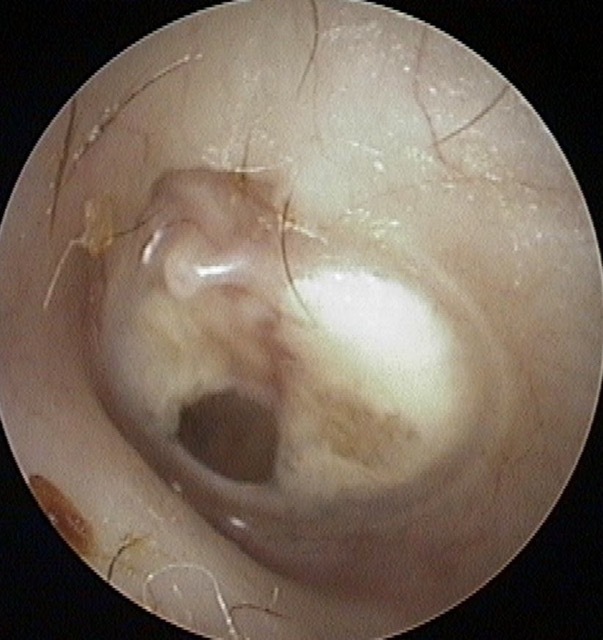

Perforation